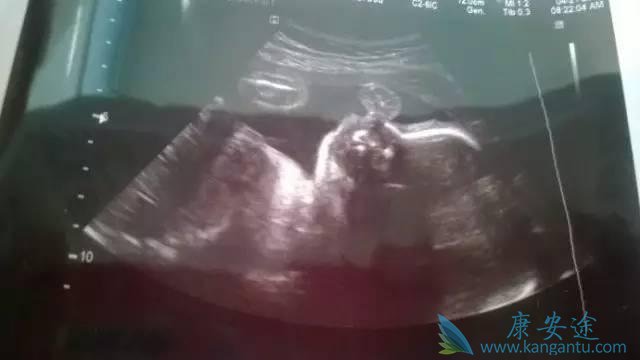

第四次B超检查—18-24周

这是整个孕期最全面的一次超声检查,它还有一个孕妈们最熟悉的名称——“大排畸”检查。为了提高病变检出率,医院基本都是采用清晰度更高的三维或四维彩超进行系统超声检查。此次检查最重要目的是观察胎儿全身各系统结构是否存在畸形,主要包括颅内结构、颜面、心脏、胃泡、肾脏、膀胱、脊柱、四肢等,如果条件良好,还能够建立宝宝的面部三维图像。

准妈妈们可以看到肚子里宝宝的容貌,甚至宝宝的动作和表情!大部分的胎儿畸形可在此时期被排查,但是一些小的畸形,如手指、脚趾这些小的病变很难查出来,还有一些先天异常是发展性的,到怀孕后期才出现。此外,超声也不是万能的,观察还会受胎儿体位、孕妇腹壁肥胖、羊水过多过少等条件限制无法清晰显示胎儿,所以“大排畸”依然无法百分之百排除所有的先天性疾病,这就更体现了规范的按照医生安排进行B超检查的重要性了。